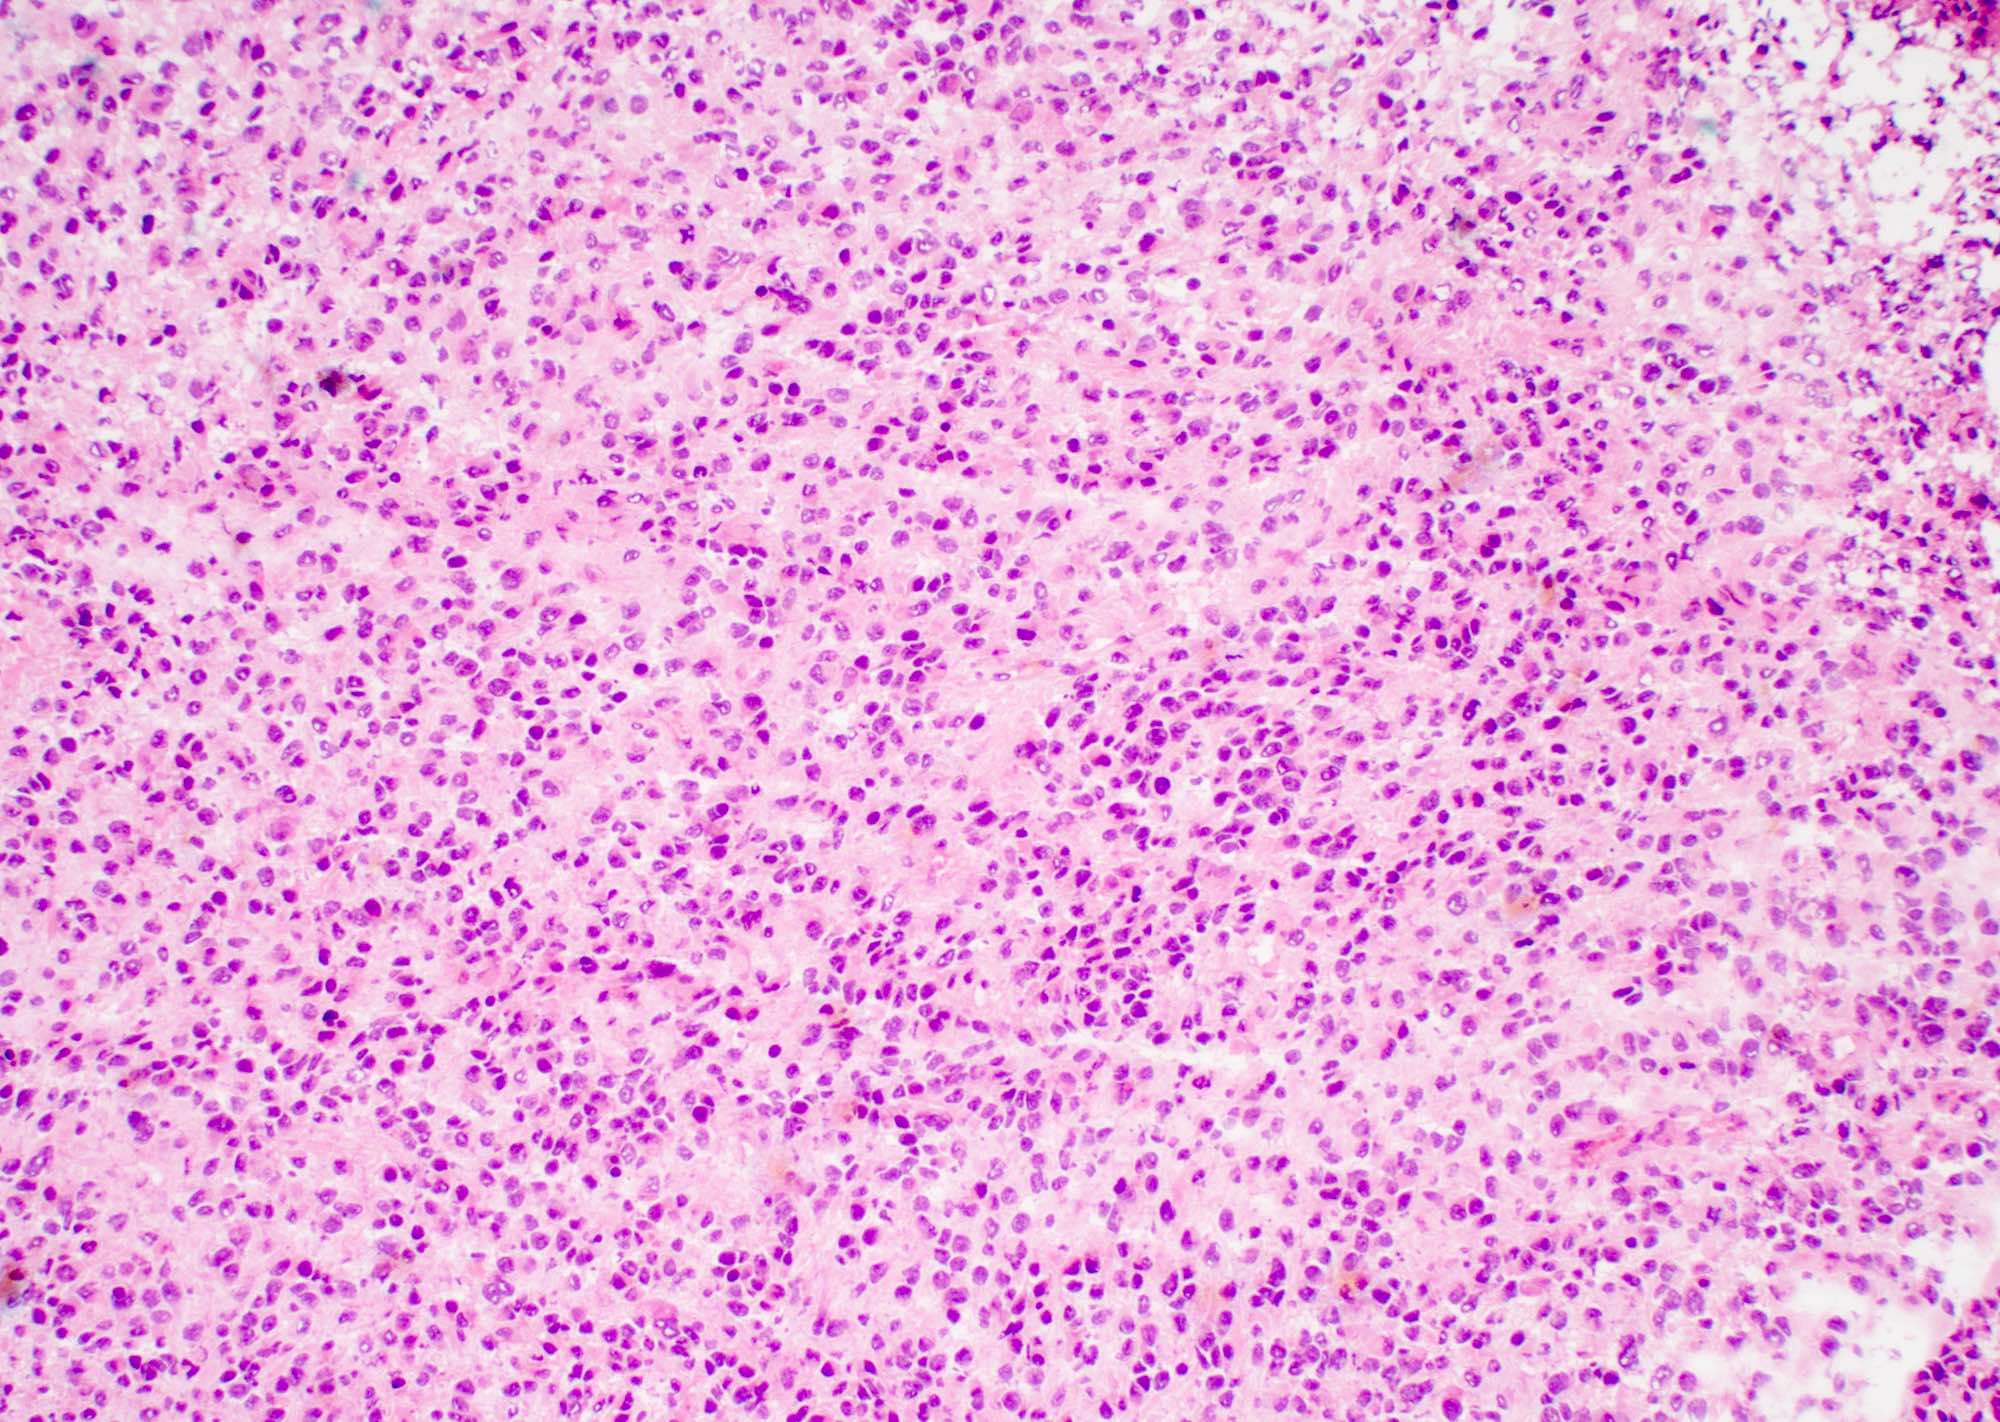

Microscopic (histologic) description

- Infiltrating, hypercellular astrocytic neoplasm often with hyperchromatic, elongated nuclei and irregular nuclear membranes

- Typically mitotically active, though not required if molecular criteria are met

- Microvascular proliferation or necrosis is required for a histologic diagnosis of GBM

- Microvascular proliferation: multilayered, small caliber vessels with glomeruloid appearance (J Neuropathol Exp Neurol 1992;51:488)

- Necrosis: can be geographic or pseudopalisading with neoplastic cells surrounding central necrosis

- Greater association of thrombosis and necrosis in IDH wild type GBM than in IDH mutant grade 4 astrocytomas (Acta Neuropathol 2016;132:917)

- Variable cell morphology: undifferentiated / primitive neuronal cells, astrocytic, gemistocytic, oligodendroglial-like, small cell, lipidized, granular, epithelioid, giant cells, mesenchymal metaplasia and epithelial metaplasia

Microscopic (histologic) images

Contributed by Bharat Ramlal, M.D. and Meaghan Morris, M.D., Ph.D.